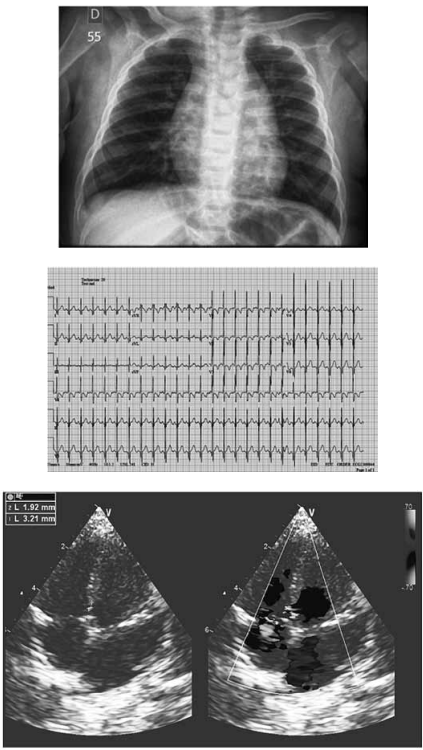

Paciente de 55 anos, feminina, vem encaminhada do Hospital de referência devido a quadro de cervicalgia associada a dor torácica esquerda de leve intensidade com piora ao esforço físico. Nega outras queixas. Tem como antecedentes: três gestações com parto cesárea sem intercorrências, ex-tabagista (carga baixa), etilista social, sedentária, diabetes mellitus não insulino dependente, osteoporose e hipertensão arterial sistêmica.

Ao exame físico: bom estado geral. FC = 75 bpm; FR = 20 irpm; PA = 160 x 70 mmHg; Saturação periférica de O2 em ar ambiente = 97% em membro superior direito e 98% em membro inferior direito. Presença de bulhas rítmicas, normofonéticas, em dois tempos e com sopro contínuo em região infraclavicular esquerda. Pulsos periféricos presentes e de amplitude aumentada.

Com base nesta figura de cateterismo cardíaco, qual a cardiopatia congênita diagnosticada?